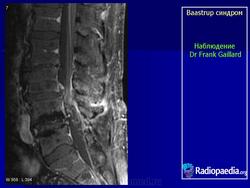

Baastrup синдром

"Бааструпа (Baastrup) болезнь, osteochondrosis interspinalis, arthrosis interspinal, kissing spine, описана в 1932 г. Характеризуется наличием хронических воспалительных изменений в остистых отростках позвонков. Вследствие этого возникают длительно удерживающиеся боли в поясничном отделе позвоночника, особенно при чрезмерном изгибе его кзади или чрезмерной нагрузке (поднимание тяжестей), с местной болезненностью в области остистых отростков. На рентгенограмме видны расширенные остистые отростки со склеротическими краями, иногда на верхнем или нижнем крае отростка остеофиты, которые могут даже соприкасаться между собой. Этиология-врожденное, неправильное развитие остистых отростков поясничных позвонков; заболевание наблюдается в определенном возрасте (30-40 лет) и у людей определенных профессий (грузчики).

Следует учитывать и относительную частоту неоартроза между остистыми отростками - межостистый диартроз (Meyer Н., 1924), «целующиеся отростки» (BrailsfordJ., 1929; Baastrup С, 1933). Синдром Бааструпа может сопровождать межпозвонковый остеохондроз (Forrai J., Tannai J., 1962). Е.С.Заславский и соавт. (1973) среди больных поясничным остеохондрозом определяли клинические и рентгенологические признаки синдрома Бааструпа в 5,5%. Боли при данном синдроме по характеру тупые, ноющие, сверлящие. Они усиливаются после длительного сидения, переноски тяжестей, при разгибании туловища. Выявляются болезненность и ограничение подвижности позвоночника (особенно в позе разгибания) на уровне пострадавших двигательных сегментов, болезненность при пальпации соответствующих межостистых промежутков. При вызывании феномена вибрационной отдачи в области поясничных межостистых связок боли, как правило, не только усиливаются, но и иррадиируют в пределах скле-ротома: в крестец, ягодицу, бедро. Инфильтрация же 1-2 мл 1% раствора новокаина межостистого промежутка быстро снимает эти феномены. Синдром связывают с поясничным гиперлордозом, структуральным сколиозом, переломом и вывихом позвонков, деформирующим спондилезом с аномальным увеличением остистых отростков. С.А.Рейн-берг (1964) относил изменения остистых отростков при данном синдроме к явлениям патологической перестройки костной ткани, обусловленной нагрузками чрезмерной силы на задние отделы позвоночного столба. Согласно N.Fellmann (1964), формирование сустава между остистыми отростками проходит следующие стадии: межостистый остеосклероз, фасетирование и склероз, тяжелое артрози-рование, анкилоз.

Baastrup синдром

Болезнь Бааструпа

Рисунок 1